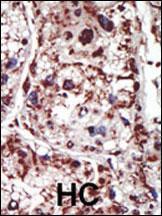

Supportive validation

- Submitted by

- Abcepta (provider)

- Main image

- Experimental details

- "Formalin-fixed and paraffin-embedded human cancer tissue reacted with the primary antibody, which was peroxidase-conjugated to the secondary antibody, followed by DAB staining. This data demonstrates the use of this antibody for immunohistochemistry; clinical relevance has not been evaluated. BC = breast carcinoma; HC = hepatocarcinoma."

- Primary Ab dilution

- 1:50~100